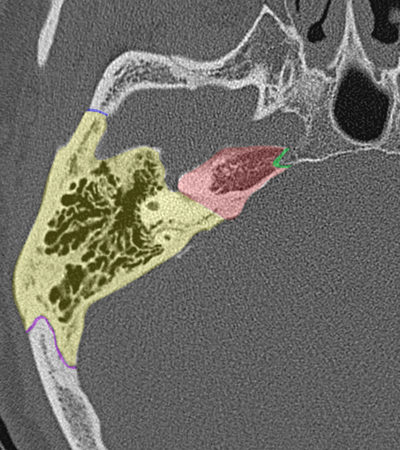

Radioanatomie du rocher sur coupes TDM

Différentes coupes de référence (A. Attyé 2013)

Coupe axiale passant par le canal semi-circulaire supérieur Coupe axiale passant par le canal semi-circulaire latéral Coupe axiale passant par le modiolus de la cochlée Coupe axiale passant par la fenêtre ronde Coupe axiale passant par le ganglion géniculé Coupe axiale passant par l'articulation incudo-malléaire Coupe axiale passant par la partie pétreuse de l'artère carotide interne Coupe axiale passant par le nerf tympanique

Coupe axiale passant par le foramen styloïde Coupe coronale passant par le muscle tenseur du tympan Coupe coronale passant par le recessus epitympanique Coupe sagittale passant par le segment mastoïdien du nerf facial coupe sagitalle oblique passant par le canal semi-circulaire supérieur (plan de Pöschl) Reconstruction axiale passant par le plan de l'étrier Coupe axiale passant par les apex pétreux